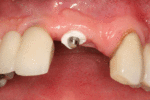

The area of the mouth that is missing a tooth is identified.

An area with a single missing tooth

A healing abutment is attached to the implant fixture and the gingiva flap is sutured around the healing abutment.

A healing abutment is attached to the implant fixture, and the flap of gingiva is sutured around the healing abutment.